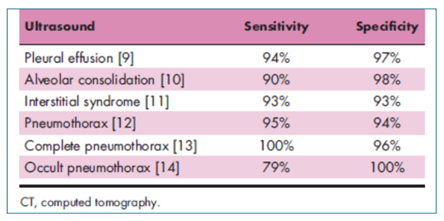

Lung ultrasound’s accuracy in almost all diagnostic testing is measured in terms of its sensitivity and specificity. Due to advances in ultrasound imaging capabilities and technologies, ultrasound exams have proven to be as good, in most cases, at evaluating abnormalities within the lung compared to CT (Figure G). In addition, many POCUS systems now feature new artificial intelligence (AI) enabled tools to simplify workflow, reduce exam times, and ultimately help clinicians increase diagnostic confidence.

Figure G. Shows the accuracy of lung ultrasound in the critically ill compared with CT. Source Lichtenstein D, Curr Opin Crir Care 2014:20:315-322.